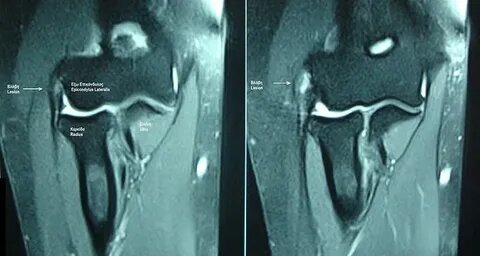

В случае сомнений можно сделать МРТ для лучшей визуализации синовиальных складок, оценки отека костного мозга.

Эпикондилит на МРТ.